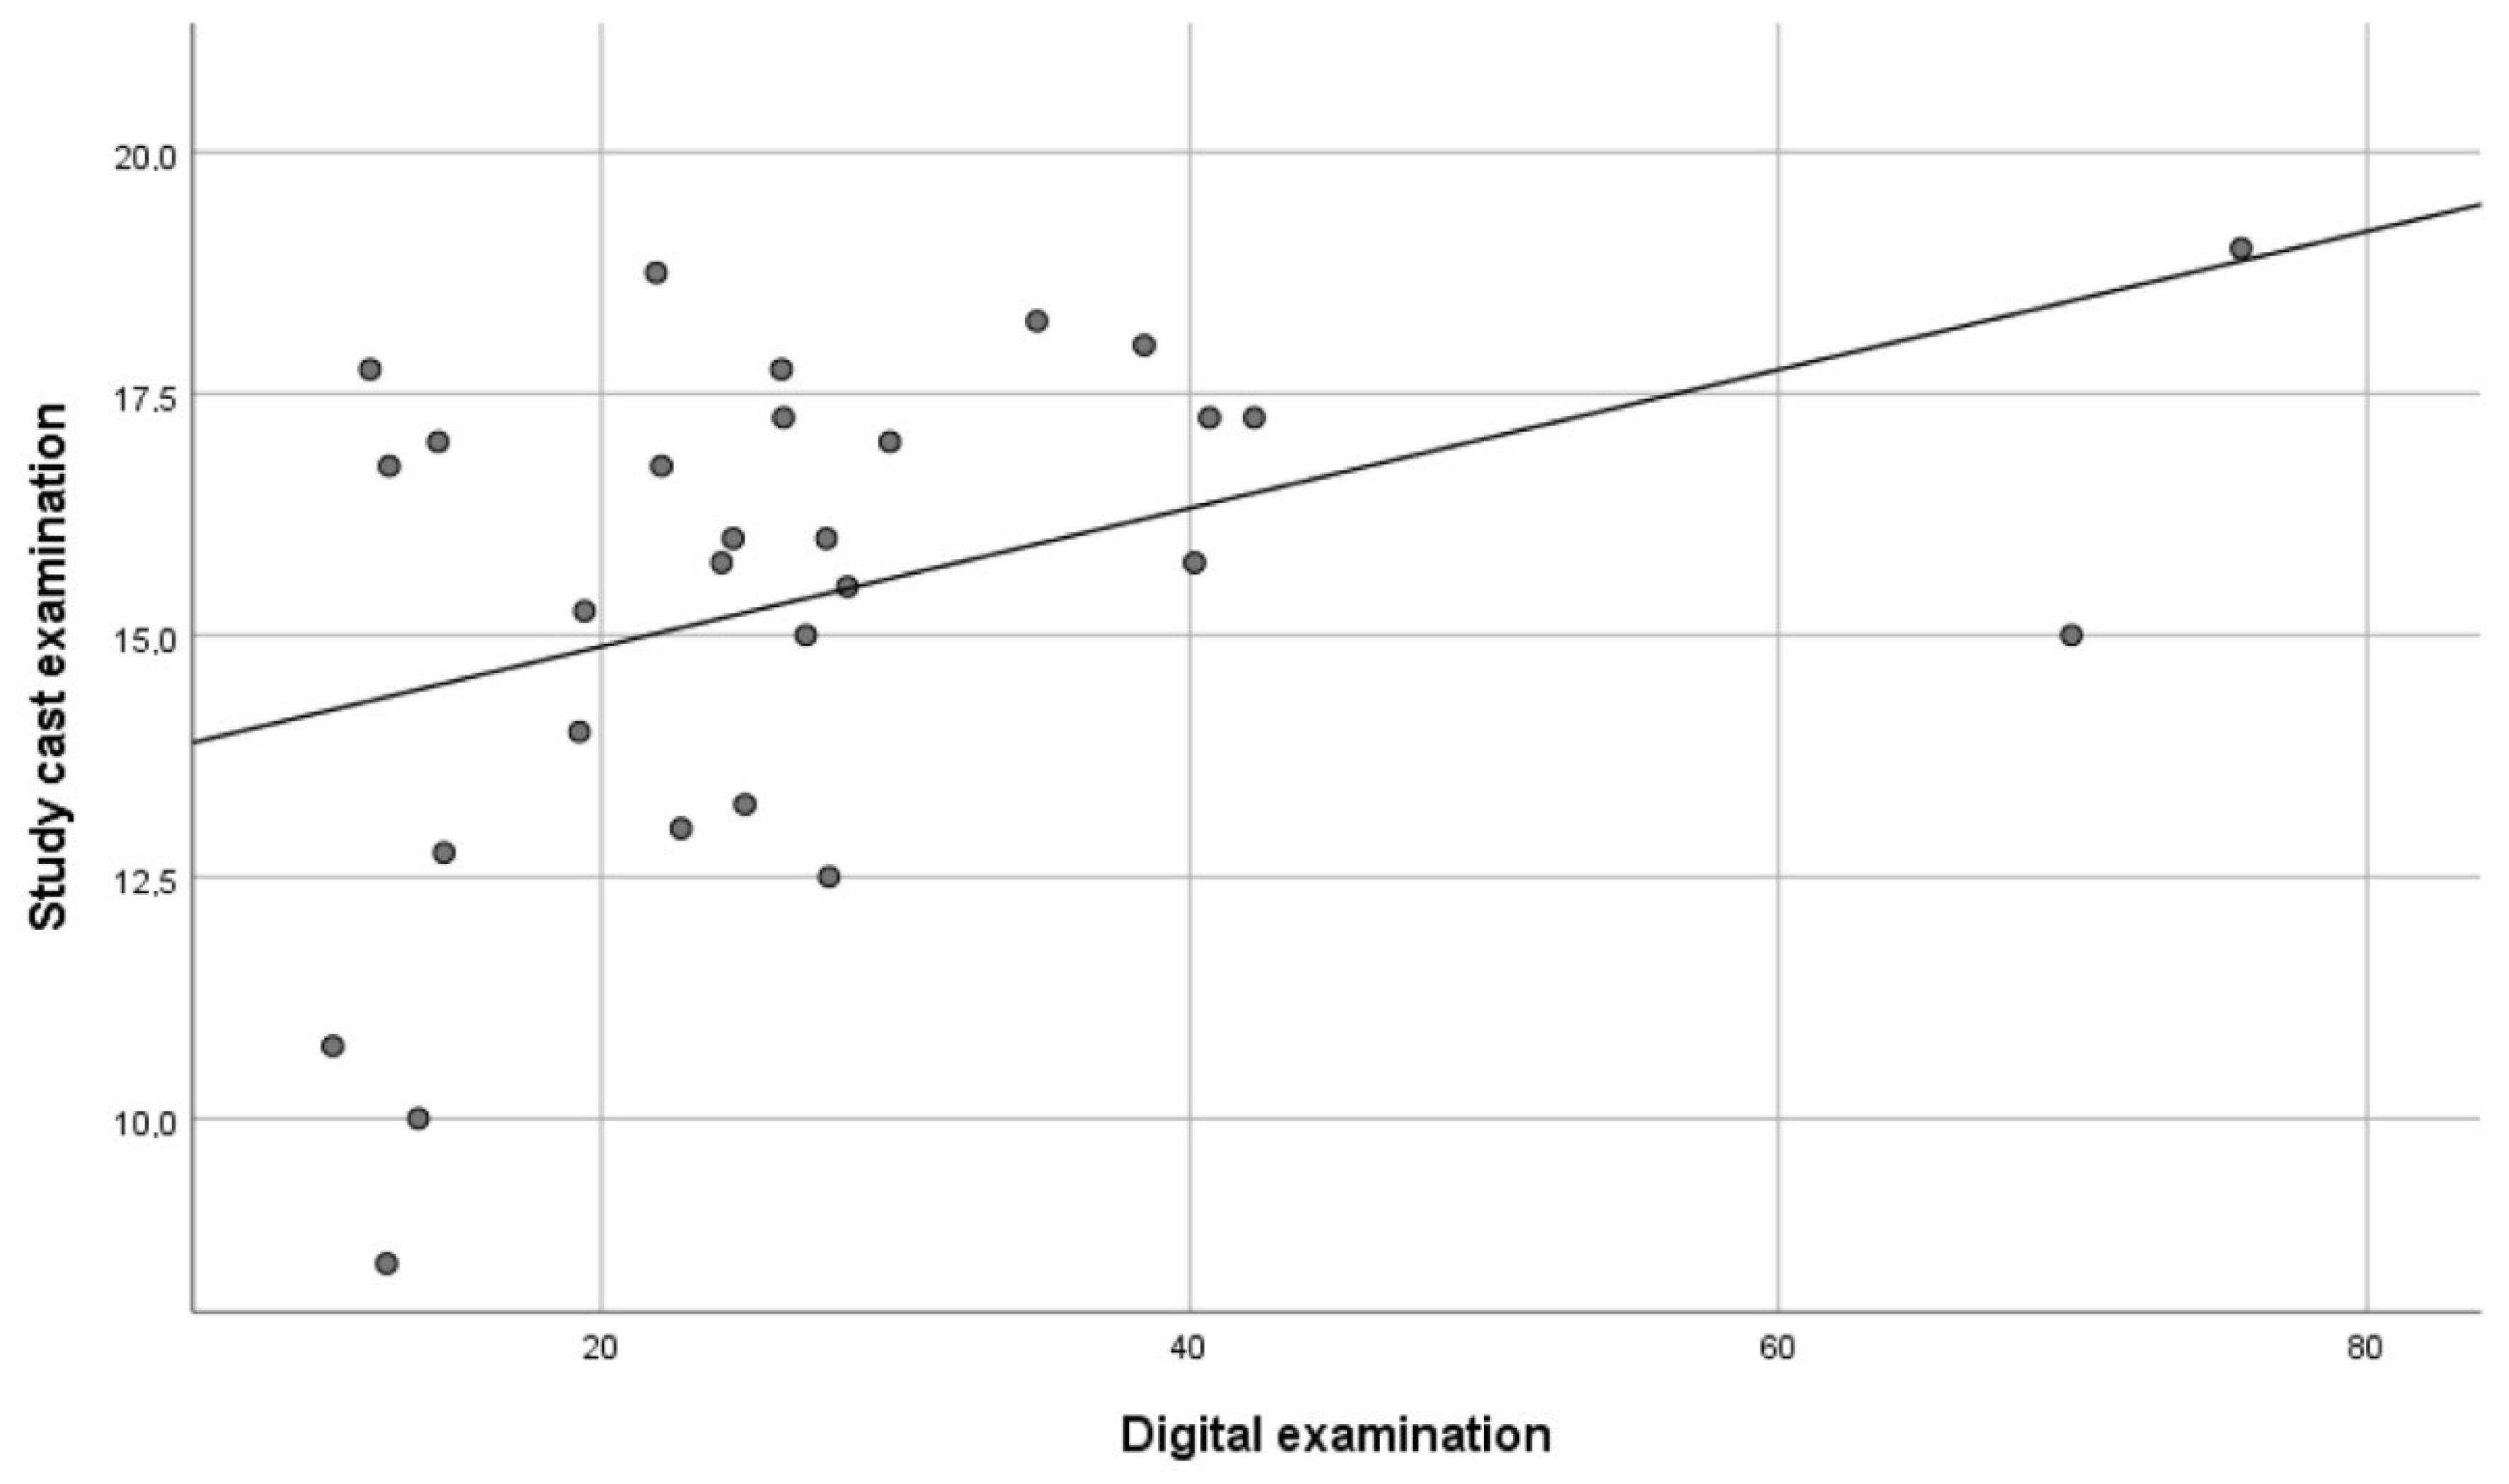

- a practical study cast examination with the measurement of the total number of occlusal contacts on stone casts mounted in an articulator (AE method);

- a digital examination with the measurement of the total occlusal contact area in millimeters (DE method).

3. Results